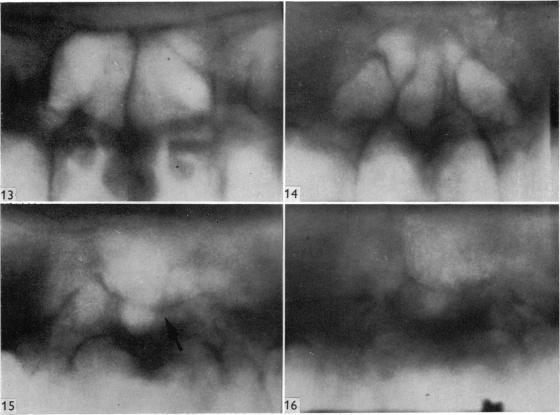

Surgical aspects of the anatomy of the sphenoidal sinuses and the sella turcica.

J Anat. 1977 Dec;124(Pt 3):541-53.